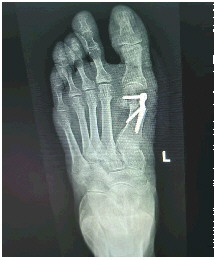

术后影像

术中,于硬膜外麻醉下手术医生依托精密动力系统,分别在其左足第1跖趾关节外侧、第1跖骨远端内侧做长约0.5厘米和2.5厘米的纵行切口,沿第1跖骨颈截骨,于近端髓腔置入一枚 外翻远端板予以固定。手术过程顺利,患者术后第2天即可下地行走。

微创 外翻矫形术不仅成功矫正了困扰张女士多年的畸形 趾,也彻底解除了伴随多年的疼痛,一家人终于舒展了眉头。术后一周内,张女士康复出院,激动地连连道谢。对于老年患者而言, 外翻常被误认为是“年纪大了都会这样”而不予重视。实际上,长期足趾畸形会导致足底压力分布异常,继而出现足底疼痛、胼胝(老茧)、鸡眼,甚至影响膝关节和髋关节,造成代偿性劳损。济阳区人民医院四肢显微外科开展的微创矫形术,具有切口小、固定牢、下床早、活动早等优势,尤其适合高龄患者,能够帮助他们重新实现无痛行走。